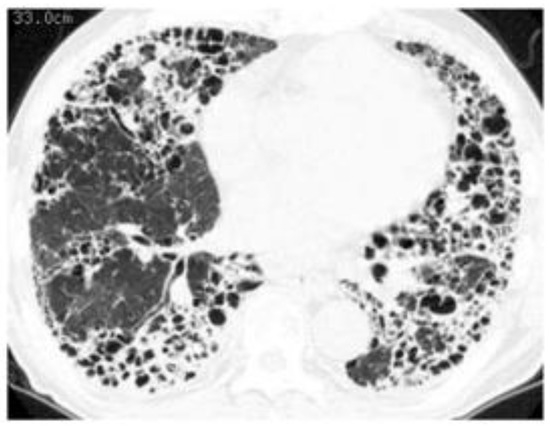

4.3. Predictors of ILD Progression and Prognostic Factors

4.4. Prognosis and Causes of Death Compared with Idiopathic Pulmonary Fibrosis